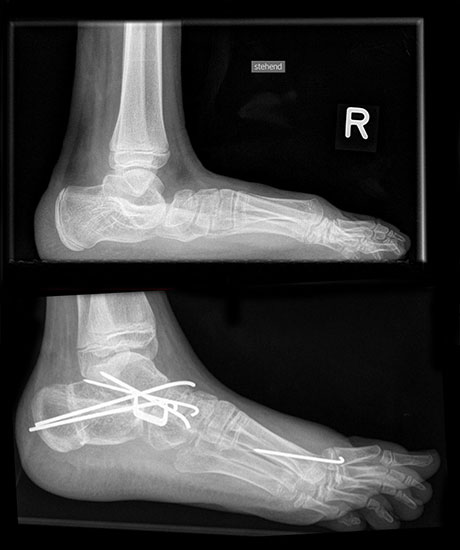

Abbildung 1: Extremer Knick-Hackenfuß beidseits mehr massiven Druckstellen aber ohne Beschwerden. Patient läuft sicher mit Konfektionsschuhen und wünscht keine operative Behandlung.

Abbildung 1